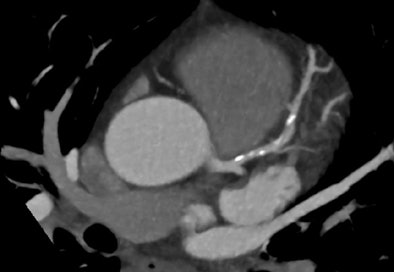

| A second contrast-enhanced acquisition (prospective ECG-triggered at 70% RR with no padding, b26f kernel with a reduced z-axis to cover the proximal coronary arteries, dose-length product [DLP] = 60) was performed nine minutes after two sprays of sublingual nitrate and additional 10 mg IV metoprolol to achieve a heart rate of 53 bpm. Contrast-phase timing is improved on the second acquisition (images above), with less contrast in the pulmonary circuit (332 HU versus 167 HU) and more contrast in the aorta and coronary arteries (365 HU versus 382 HU). Total DLP for all three acquisitions was 175 mGy/cm, for a total effective dose of 2.45 mSv. Of interest, the luminal diameter of the proximal LAD increased from 8.0 mm2 to 12.6 mm2 after sublingual nitrate (image below). The final images show eccentric, positively remodeled, calcified plaque in the LAD with mild (25% to 49%) sequential stenoses but no significant obstructive lesion (images above). Also of note, cardiac MR was performed on the same day to quantify left ventricular function, right ventricular function, and left ventricular mass due to history of hypertension, revealing a left ventricular ejection fraction of 57%, and left ventricular mass/index of 126 g/m2 indicating mild left ventricular hypertrophy. The patient's medical therapy was increased with the addition of ezetemibe to a potent statin, aiming for an LDL of < 1.5 mmol/L (< 58 mg/dL), and an ACE inhibitor added for hypertension and atherosclerosis control. This case illustrates the importance of heart rate control, sublingual nitrates, review of images at the time of acquisition, choosing the appropriate acquisition protocol to suit the patient heart rate and patient size. |